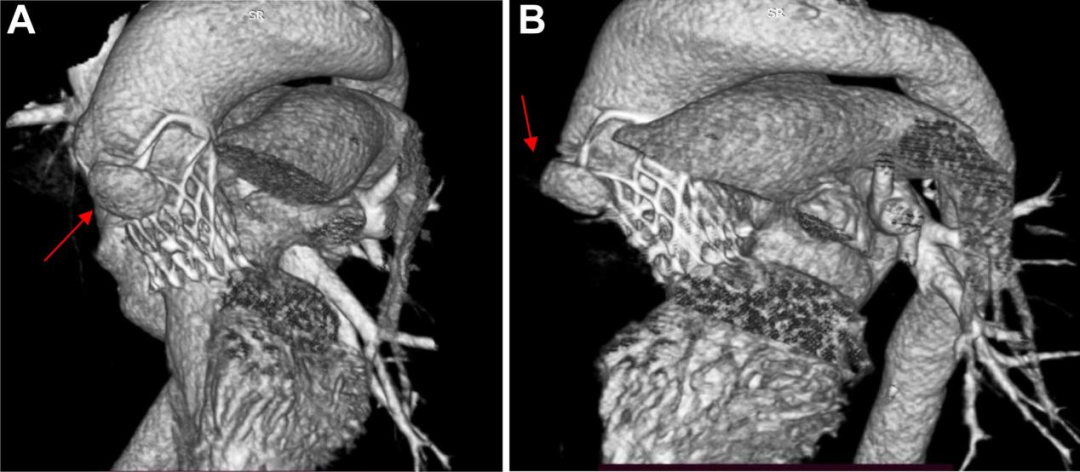

病史摘要:64岁男性患者,因“反复胸闷2月”入院。既往有10年高血压病史,最高血压160/100 mmHg,长期服药后血压控制在130/80 mmHg左右;20年前行胆囊切除术,有胰腺炎病史,否认糖尿病等慢性及传染病史。劳累后心前区闷痛,持续约5分钟,休息可缓解,入院时仍时有胸闷。 诊疗过程:查体血压130/80 mmHg,心率80次/分,律不齐,主动脉瓣第一听诊区闻及收缩期喷射样杂音